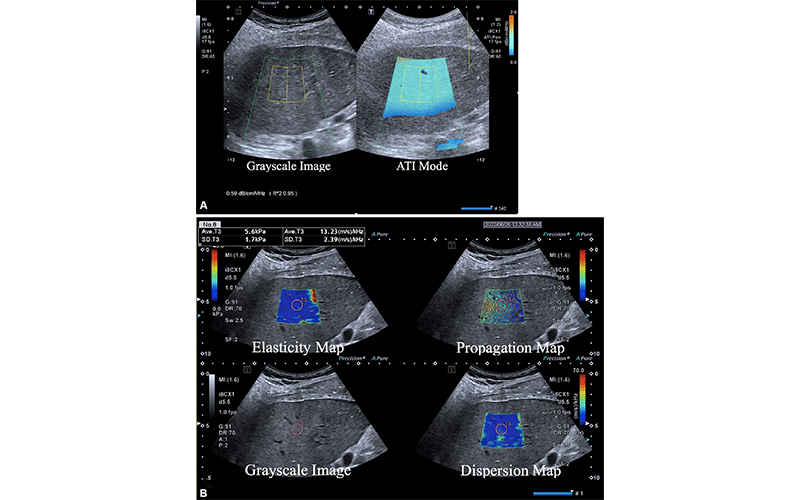

Multiparametric US in a 52-year-old female patient with metabolic dysfunction–associated fatty liver disease (MAFLD) and hepatitis B, whose body mass index was 26.9 (calculated as weight in kilograms divided by height in meters squared). (A) Gray-scale image (left) shows the liver parenchyma, and attenuation image (ATI) (right) shows the right liver lobe acquired from the right intercostal oblique plane, with the degree of attenuation color-coded in the sampling box. Orange indicates a high attenuation coefficient (AC) and blue indicates a low AC. The AC value (0.59 dB/cm/MHz) and reliability index (R2 = 0.95) are presented in the lower left corner. (B) Two-dimensional shear-wave elastography–generated quad-view mode image shows an elasticity map, propagation map, gray-scale image, and dispersion map at the same time. A 1-cm region of interest is placed within the sampling box of each image. Red and blue indicate high and low elasticity and dispersion slope, respectively. Liver stiffness on the elasticity map is 5.6 kPa, and the dispersion slope on the dispersion map is 13.23 (m/sec)/kHz. https://doi.org/10.1148/radiol.232416 © RSNA 2024